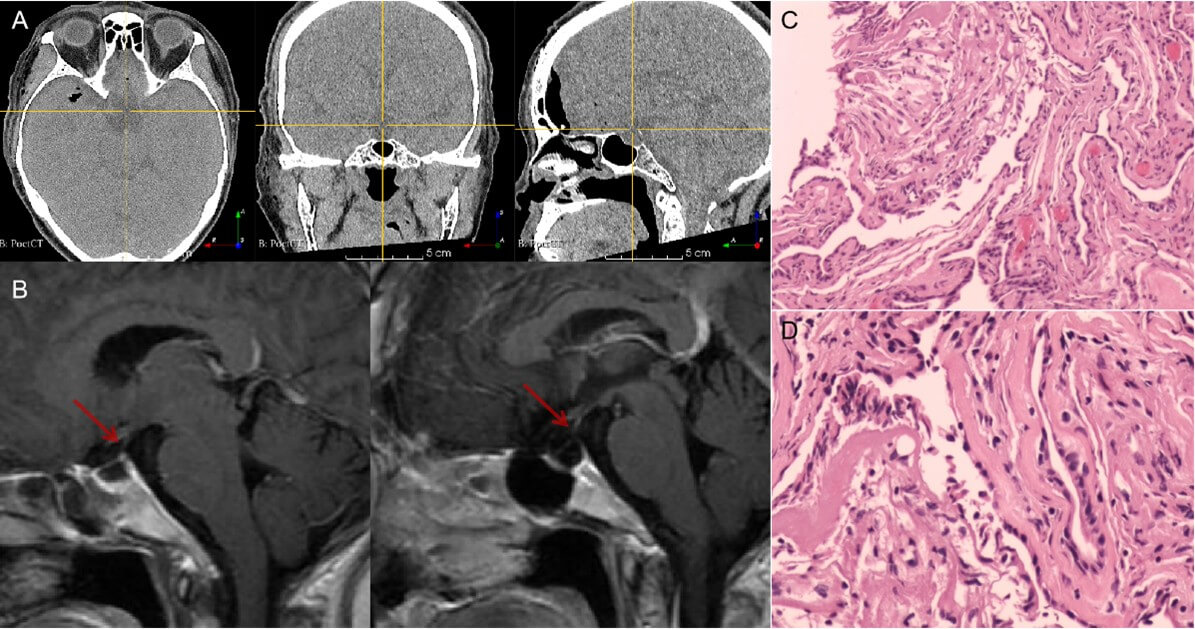

7. Clinical Outcomes (Figure 5)

The patient recovered uneventfully without postoperative complications such as fever or diabetes insipidus. The scalp incision healed well. Follow-up CT showed no surgical site hemorrhage, while MRI demonstrated complete resolution of the sellar cyst with preserved pituitary gland and stalk anatomy. Pathological examination confirmed the diagnosis of a benign cyst.